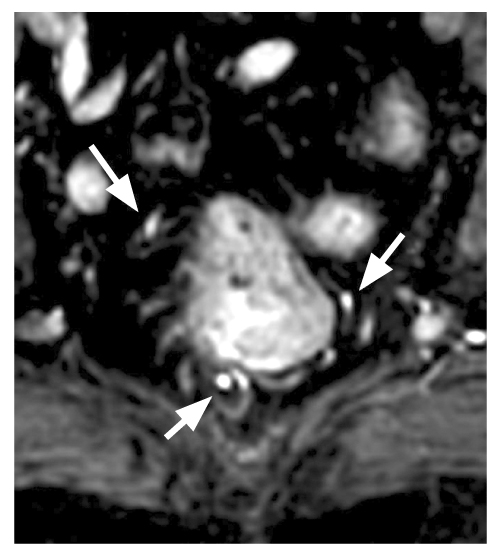

Во всех случаях, пригодных для интерпретации, определялось по 6 терминальных ветвей верхней прямокишечной артерии, локализованных на 1, 3, 5, 7, 9 и 11 часах условного циферблата (рис. 2). Следует отметить большое (7) число выявленных анатомических вариантов ветвления верхней прямокишечной артерии и способа достижения стенки прямой кишки (рис. 3, табл. 1). При этом на классический вариант ветвления верхней прямокишечной артерии на 3 ветви с последующей бифуркацией каждой приходилось 54% случая (на рис. 3 это, соответственно, 1, 5 и 6-й варианты); рис. 4, 5.

Рис. 2. Магнитно-резонансная томография: визуализировано 6 терминальных ветвей верхней прямокишечной артерии, локализованных на 1, 3, 5, 7, 9 и 11 часах условного циферблата.